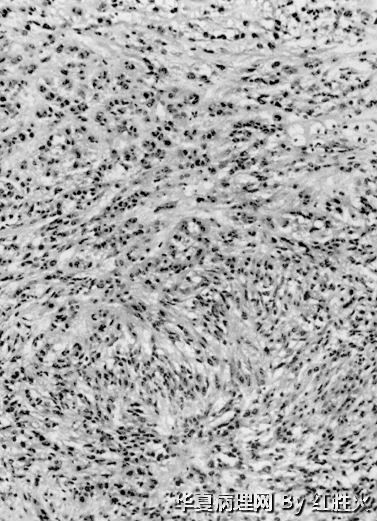

男,22岁,下肢肿物数年,无明显症状。

大体:1.5cm×1.2cm×0.8cm 囊肿一个,切开后流出淡红色液体。

临床诊断:肿物性质待查。

本例具有以下特点:

1、青年男性,下肢肿物,最大径1.5cm

2、低倍镜下见界限清楚,中央囊变,具有肿瘤细胞密集区和疏松黏液样变区,局部有模糊结节状。

3、高倍镜下观察到以下特点:(1)中等大小的血管呈管壁玻璃样变性;(2)细胞核有深染、不规则形,但罕见核分裂,类似于退变性核;(3)细胞呈卵圆形、圆形或多角形,粘液样变区可见细胞界限较清,排列方式巢、索状,细胞浆较丰富,红染;(4)可见纤维性中心的菊形团样结构。

诊断:上皮样神经鞘瘤。

免疫组化:做S-100、IV型胶原、Ki-67

鉴别诊断:主要鉴别上皮样MPNST,需镜下计数核分裂,看Ki-67指数。